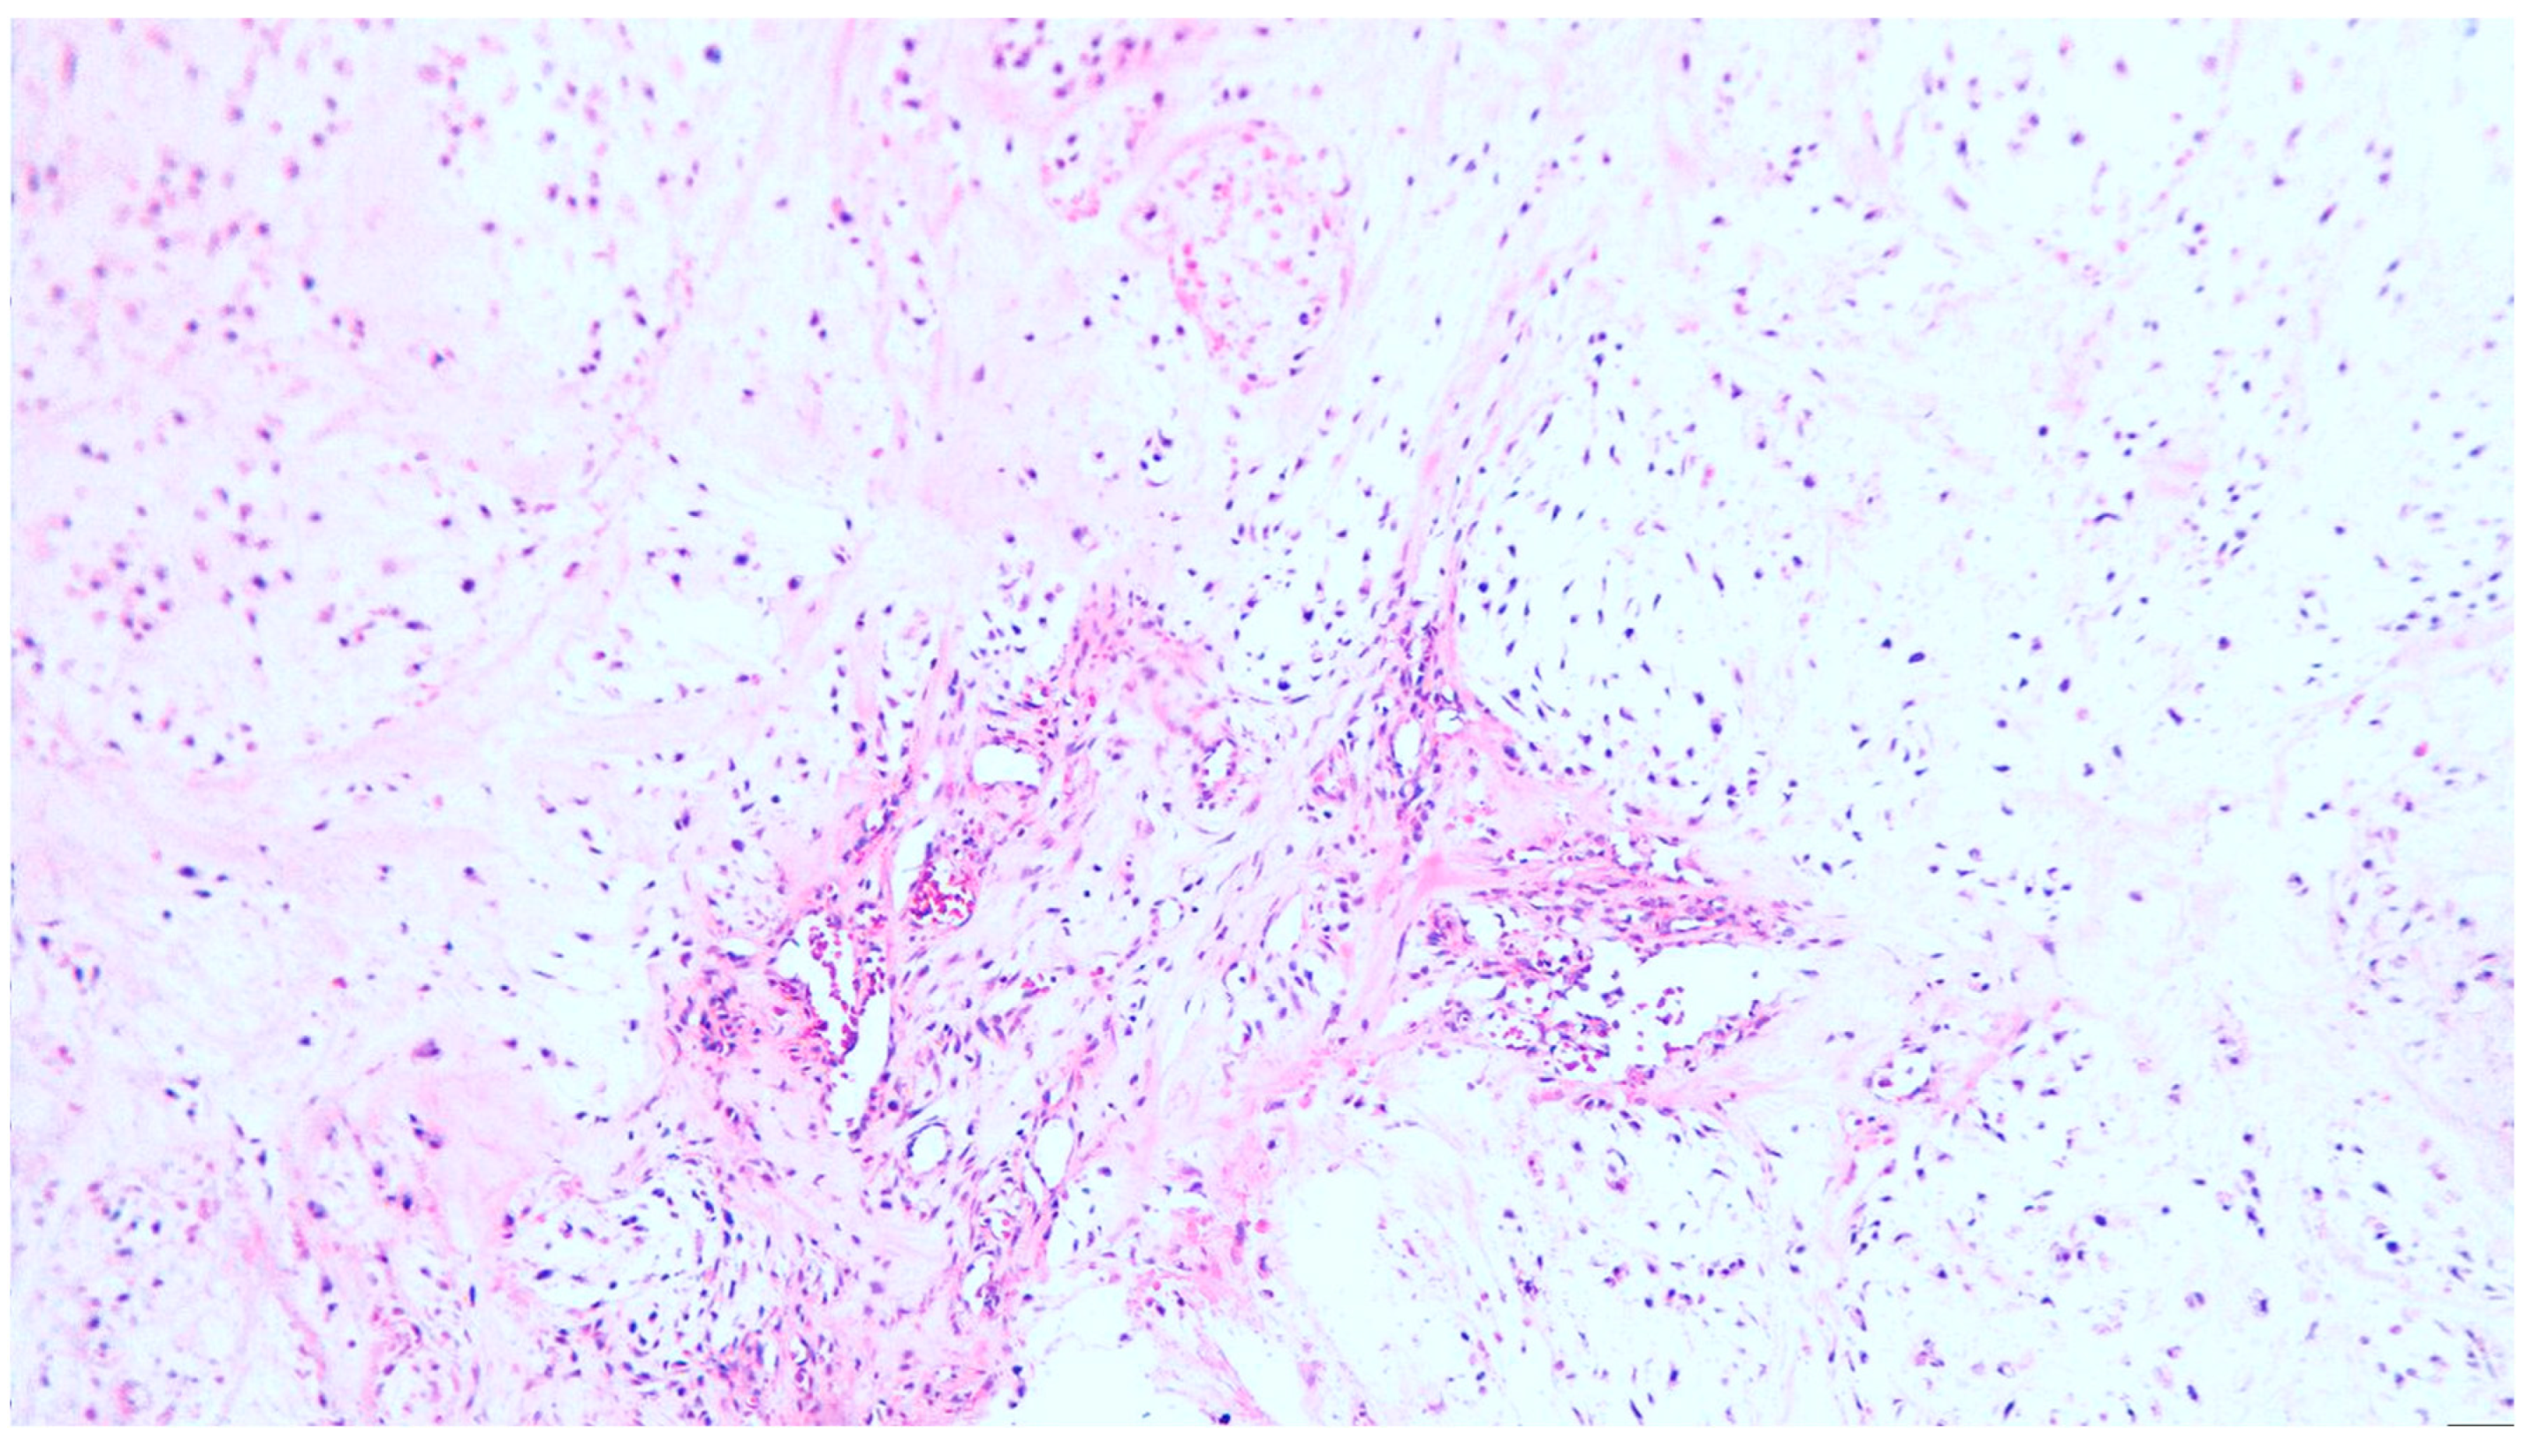

Figure 1. Chondrosarcoma grade I, with lobular growth pattern, lobules separated by fibrous bands containing small blood vessels, hematoxylin and eosin (H&E) staining, x100 magnification.